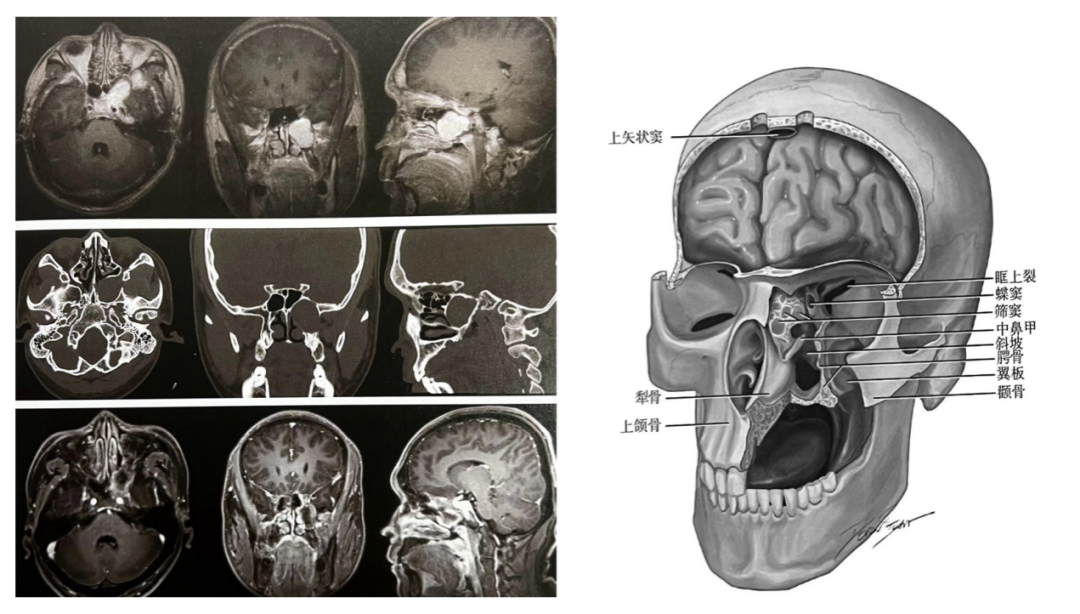

复杂脑肿瘤及颅内外沟通性肿瘤的手术治疗是神经外科领域的一项具有挑战性的任务,这些肿瘤往往因其位置特殊、结构复杂、与周围组织(血管及神经)关系密切而增加了手术的难度,需要医生具备高超的手术技巧和丰富的临床经验,也常需要多学科团队的协作。我们科室常与耳鼻喉科、口腔颌面外科、头颈外科、肿瘤科等协同合作,能实现最大范围的安全切除,确保患者得到全面的治疗和护理。

7

大脑深部肿瘤由于其位置深在,周围结构复杂,给手术治疗带来了极大的挑战。脑干是生命中枢所在地,脑干肿瘤手术风险极高。大脑深部肿瘤及脑干肿瘤的显微外科手术治疗是一项复杂而精细的技术,我们通过高超的手术技巧、丰富的临床经验及一流的硬件设备,为这类患者带来个体化的精准治疗,从而达到最佳的治疗效果。